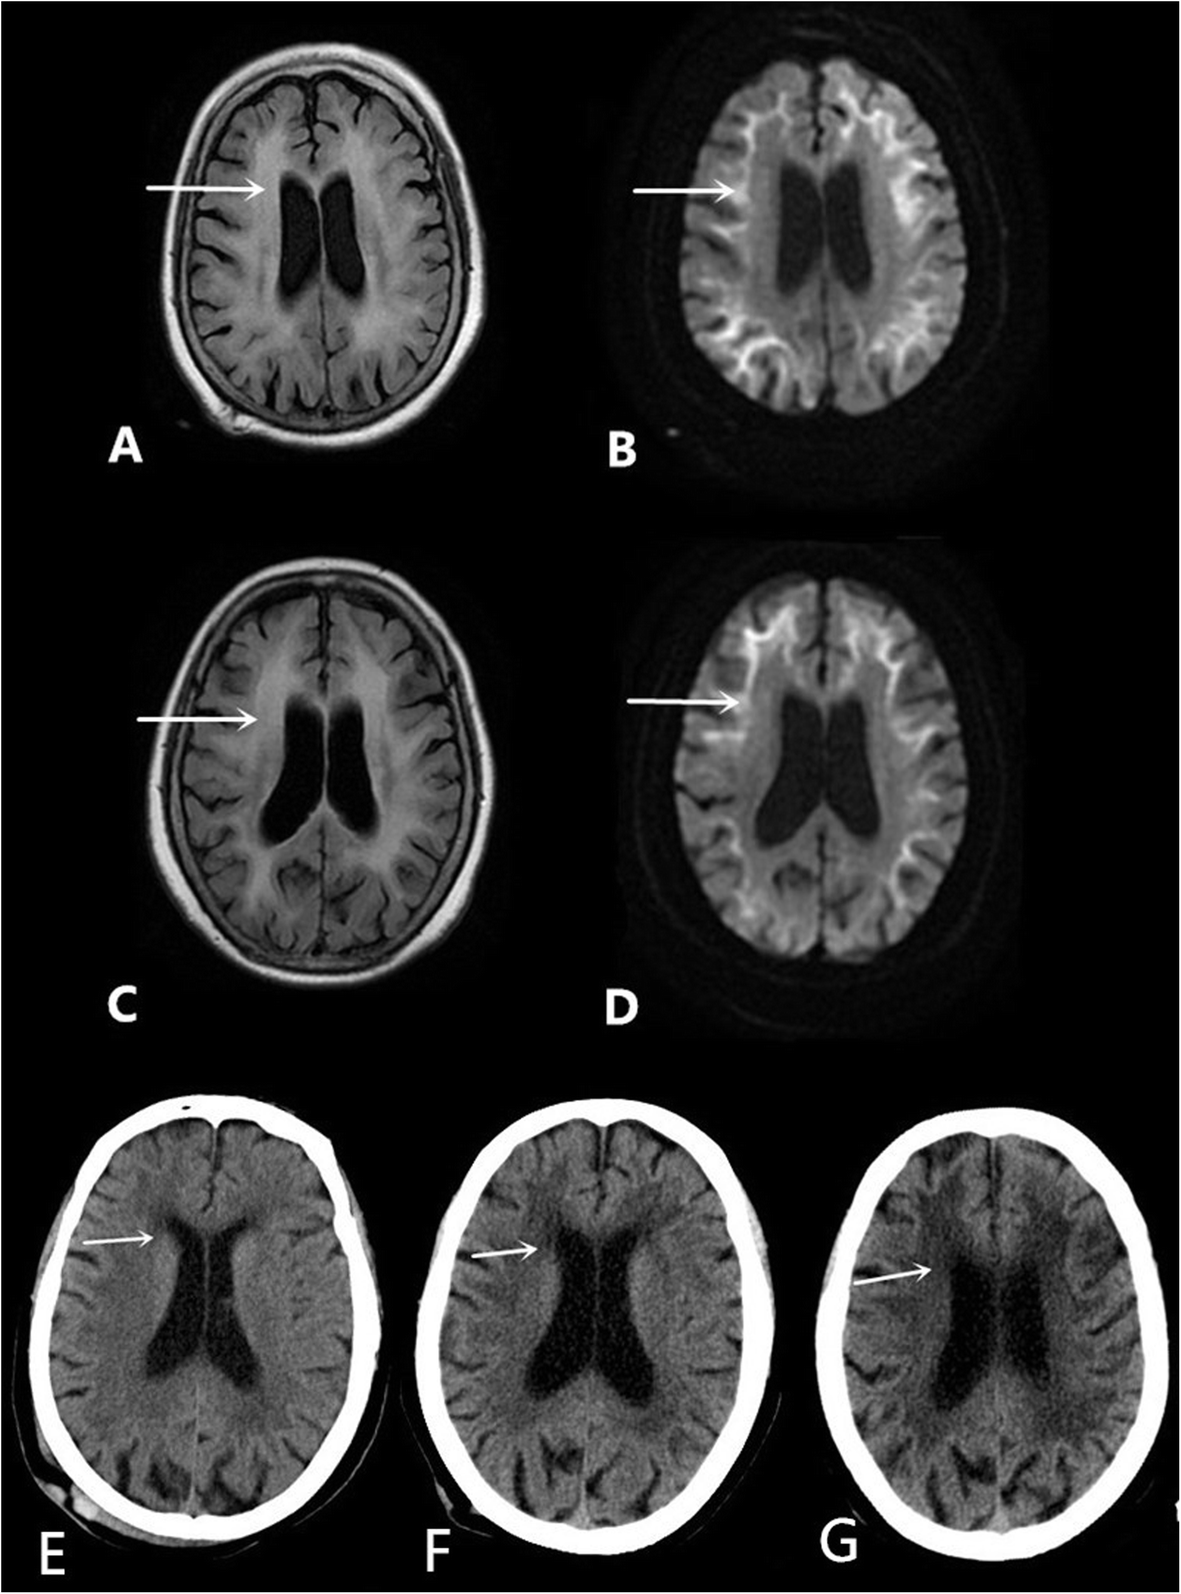

Fig. 1

MRI scans on the 5th day after admission: a The T2/FLAIR sequence: the arrow refers to abnormal signals in the white matter region of the brain, b DWI imaging: the arrow refers to high intensity areas in the cerebral white matter and grey matter-white matter junction; the MRI was conducted on the 20th day after admission: c The T2/FLAIR sequence: the arrow refers to abnormal signals in the white matter region of the brain, d DWI imaging: the arrow refers to high intensity areas in the cerebral white matter and grey matter-white matter junction. Cranial computed tomography scans showed a low-density lesion in the white matter, area-brain atrophy, and leucoencephalopathy: e in 2012, f in 2018, and g this hospitalization